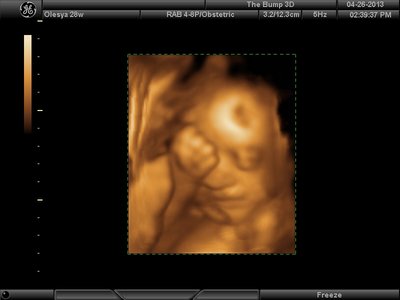

Еще одна, качество ужасное..

Вложения: |

image.jpg [ 60.32 КБ | Просмотров: 1174 ]

katerina73 писал(а): Вот, пожалуй, самая лучшая фотография. Катюш, так ваш пупсик зато отлично виден, черты лица отменно видны. Те первые две вчерашние, вторые средней дочки. Со средней черты отлично видны, с этой куклой не понятно..

Ой, Ксюнь, класс!!! Я говорю у вас у всех очертания носика, губок видны отлично...у моей же все размыто как-то и везде разное. На одной фотке вообще не нос а аэродром. Я ничего не поняла. Но УЗИстка сказала что она очень близко к плаценте мордашкой была поэтому так мутно все. Я надеюсь они мне переделают бесплатно все же. Я бы очень хотела. Так рассмотреть охото как следует, за это ведь и платила как никак..:-)

Анют, зай, это я приличные самые выставила...на других вообще нечто...меня переносица смутила с носом, хочу пересмотреть..